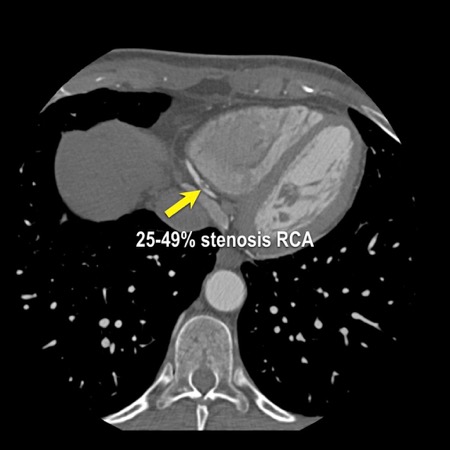

case 1 – CAD-RADS 2/P1

First, scroll through the scan.

Not all images are included. Some images without any abnormalities are skipped

from the series.

How would you describe the findings on the coronary CTA?

The findings are:

- Agatston score of

this patient was 14 (P1). Please, also note the calcification of the aortic valve. - Some partially

calcified and calcified plaques are present in the LAD with mild stenosis

(25-49%). - Calcified-plaque in

the LCX causing minimal stenosis (<25%). - Non-calcified

plaque in the distal RCA causing minimal stenosis (<25%). - This patient classifies

as CAD-RADS 2/P1, which means no further workup is needed.